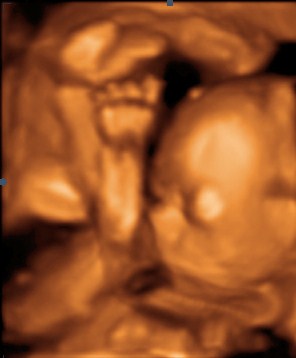

Fantorangen Skrevet 21. mars 2010 Forfatter #406 Skrevet 21. mars 2010 Da er det søndag igjen og dagene flyr synes jeg. I alle fall helgene... I går var jeg og mannen på 3-d ultralyd å så på lille frøkna. Vi har et familiemedlem som er alvorlig syk og derfor ville vi ta litt tidlig 3-d så denne personen også kunne få et inntrykk av babyen. Vi viste at bildene ikke ble helt perfekte fordi hun ikke har så mye underhudsfett på kroppen, men synes at det ikke ble så verst alikevel. Fikk mange bilder og noen videosnutter og hun var veldig villig til å vise seg frem. I tillegg var den som tok ultralyden ikke i tvil på at det er ei jente, så nå er det bare å vaske tøyet vi har arvet... Bilde av lille gullet vårt...